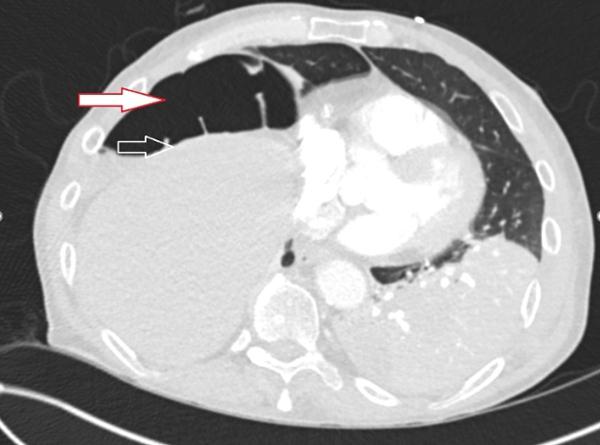

A chest x-ray done prior to intubation showed concern for free air below the right diaphragm (Image 1). A subsequent CT scan showed dense left lower lobe consolidation and confirmed a gaseous collection between the right hemidiaphragm and the liver (Image 2).